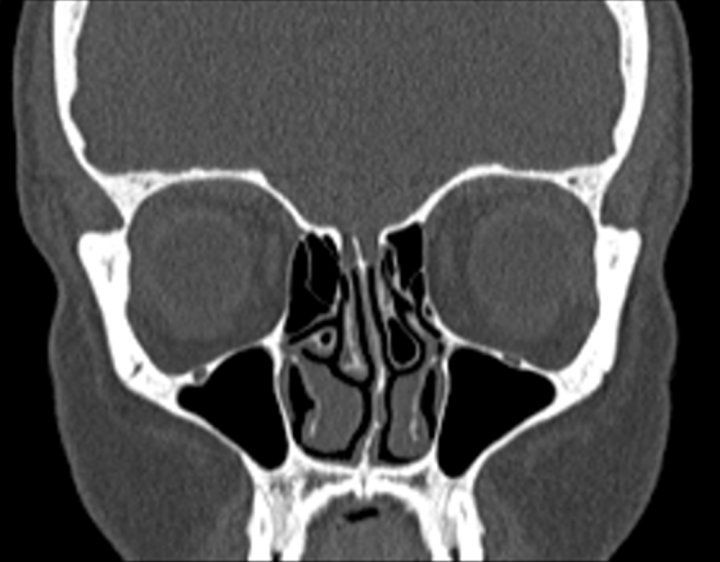

Click any image for labels.